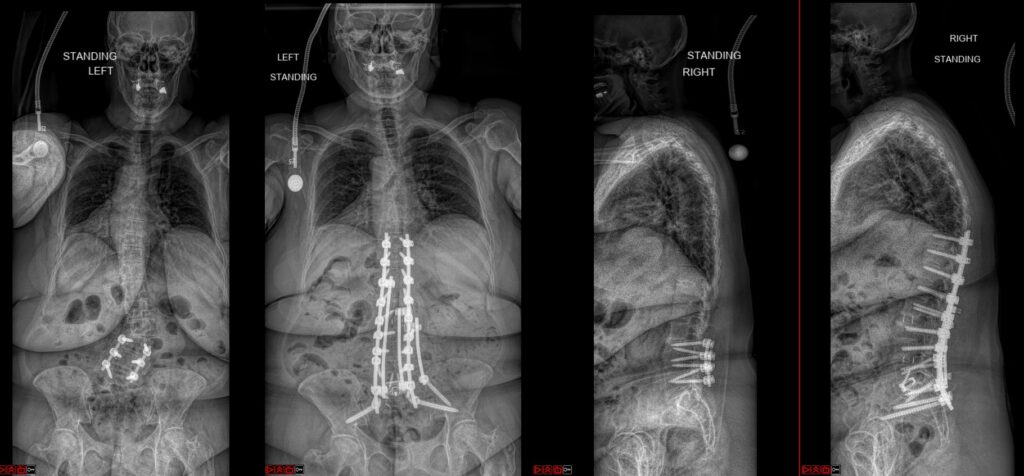

Deformity Surgery